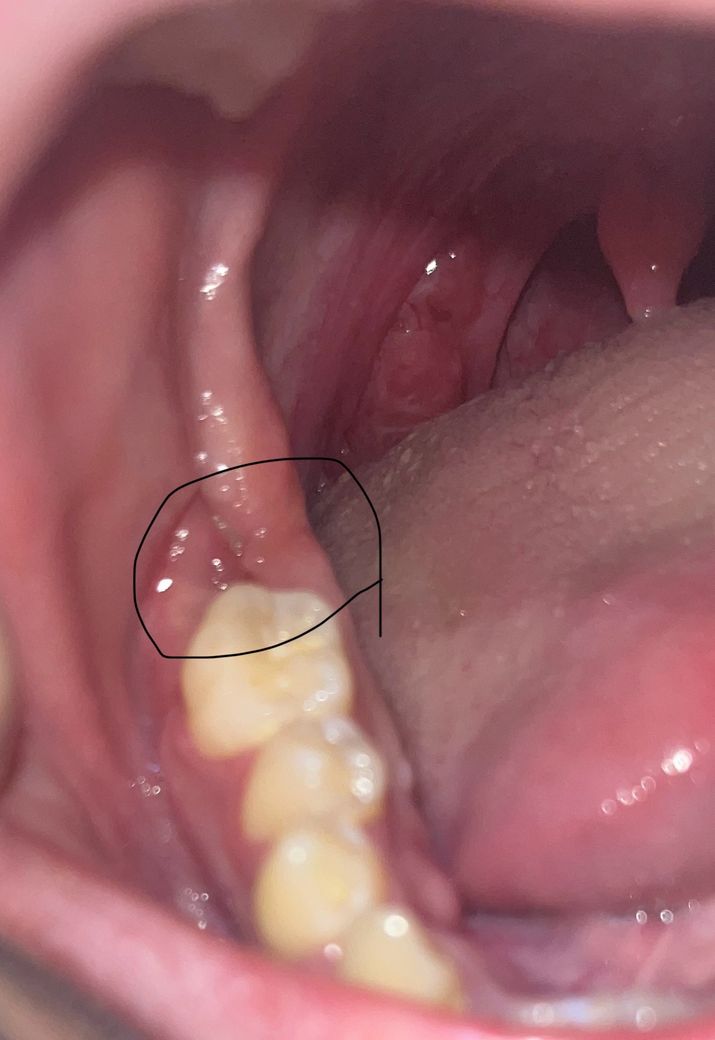

뼈이식 임플란트 실밥제거후 2주 지났는데 염증인가요?

뼈이식 임플란트 후에 실밥제거을 하고 나서 2주가 지났습니다 근데 오늘 아침부터 뭔가 조금 부은 느낌이 있어서 보았더니 조금 빨갛게 살짝 부어올라왔는데 염증이 생긴걸까요?

• 1번 째 사진

사진으로 보아서는 정확한 판단이 어렵지만 부었다면 치과를 방문하는 것이 좋습니다. 임플란트 주위에 염증이 있는 경우에 붓는 경우가 간혹 있습니다. 따라서 지체하지 마시고 임플란트를 시술한 치과를 방문하여 검사를 해보시길 바랍니다.

사진 상 눈에 띄는 염증 소견은 보이진 않습니다. 통증이 심해지거나 붓는다면 치과 가보시는 게 좋습니다.

사진상으로는 염증이 생긴것으로 보이지는 않습니다. 하지만 통증이 동반이 되는 경우에는 염증가능성이 높기에 치과 진료를 받길 권합니다.

잘 아물고 잇는거 같습니다. 염증이 있는건 아니니 걱정하지 마시고 관리를 잘해주시면될것같습니다.